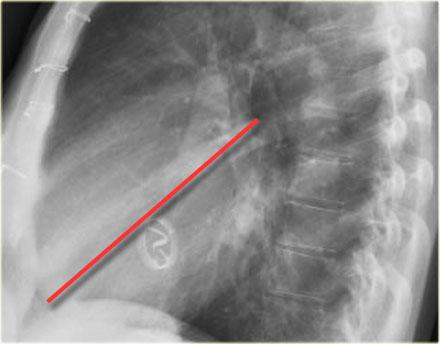

Giải Phẫu Van Tim trên X-quang Tư Thế Nghiêng

- Để xác định vị trí các van tim trên tư thế nghiêng, vẽ một đường từ carina đến mỏm tim:

- Phía trên đường: Van động mạch chủ và van động mạch phổi

- Phía dưới đường: Van ba lá và van hai lá (4)

Đường kẻ này giúp ước lượng vị trí các van tim và đánh giá tình trạng giãn từng buồng tim.

Lưu ý hình ảnh giãn thất trái mức độ nặng trên tư thế nghiêng này.